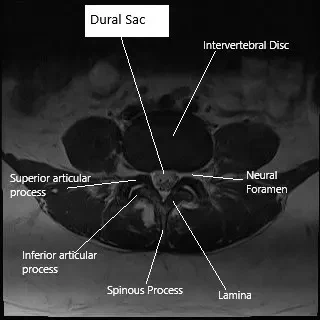

Axial section (MRI) of lumbar spine showing dural sac.

How the Body Part Normally Works? (Relevant Anatomy)

The dura is the tough, protective outer membrane surrounding the brain and spinal cord. It contains cerebrospinal fluid, which serves as a cushion and delivers nutrients to nerve tissues. Underneath the dura are finer membranes (arachnoid and pia mater) that further protect the spinal cord. When the dura is torn, CSF leaks out, lowering pressure in the brain and spinal canal. This can lead to postural headaches (worse when standing), dizziness, and nausea.